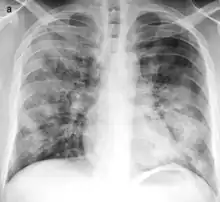

Typical distribution of lobar pneumonia (left in image) and bronchopneumonia (right in image) | |